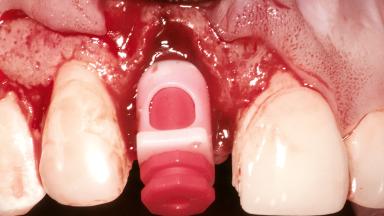

Placement Protocol | Immediate implant placement |

Socket Morphology | Multi-root socket |

Socket Integrity | Sufficient, with intact bone walls |

Bone Volume | Sufficient, with intact walls |